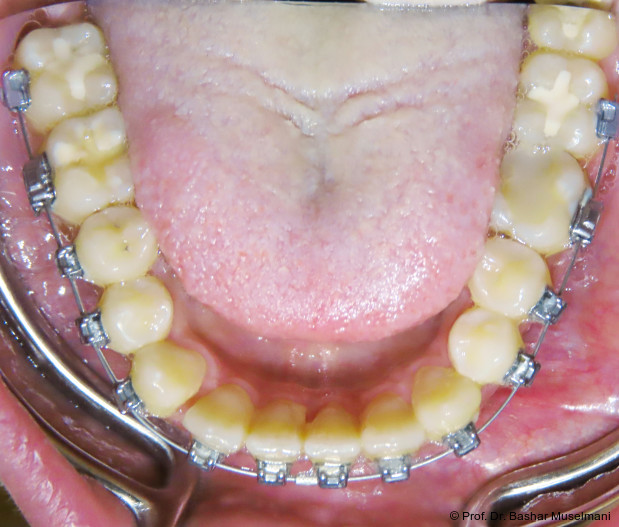

Die Abbildungen 1 bis 3 zeigen die initiale klinische und radiologische Ausgangssituation.

Apparative Versorgung

Die Behandlung erfolgte mittels einer festsitzenden Multibracketapparatur unter Verwendung passiver selbstligierender Brackets (Damon Ultima System) im Ober- und Unterkiefer.

Unterkiefer

• Zähne 33–43: Brackets mit proklinationsförderndem Torque

Hierdurch sollte eine gezielte Proklination der unteren Front zur Verbesserung des Overjets und der sagittalen Verzahnung erreicht werden.

Zu Beginn der Nivellierungsphase wurden in beiden Kiefern 0.013" CuNiTi-Bögen eingesetzt (Abb. 4a–e).